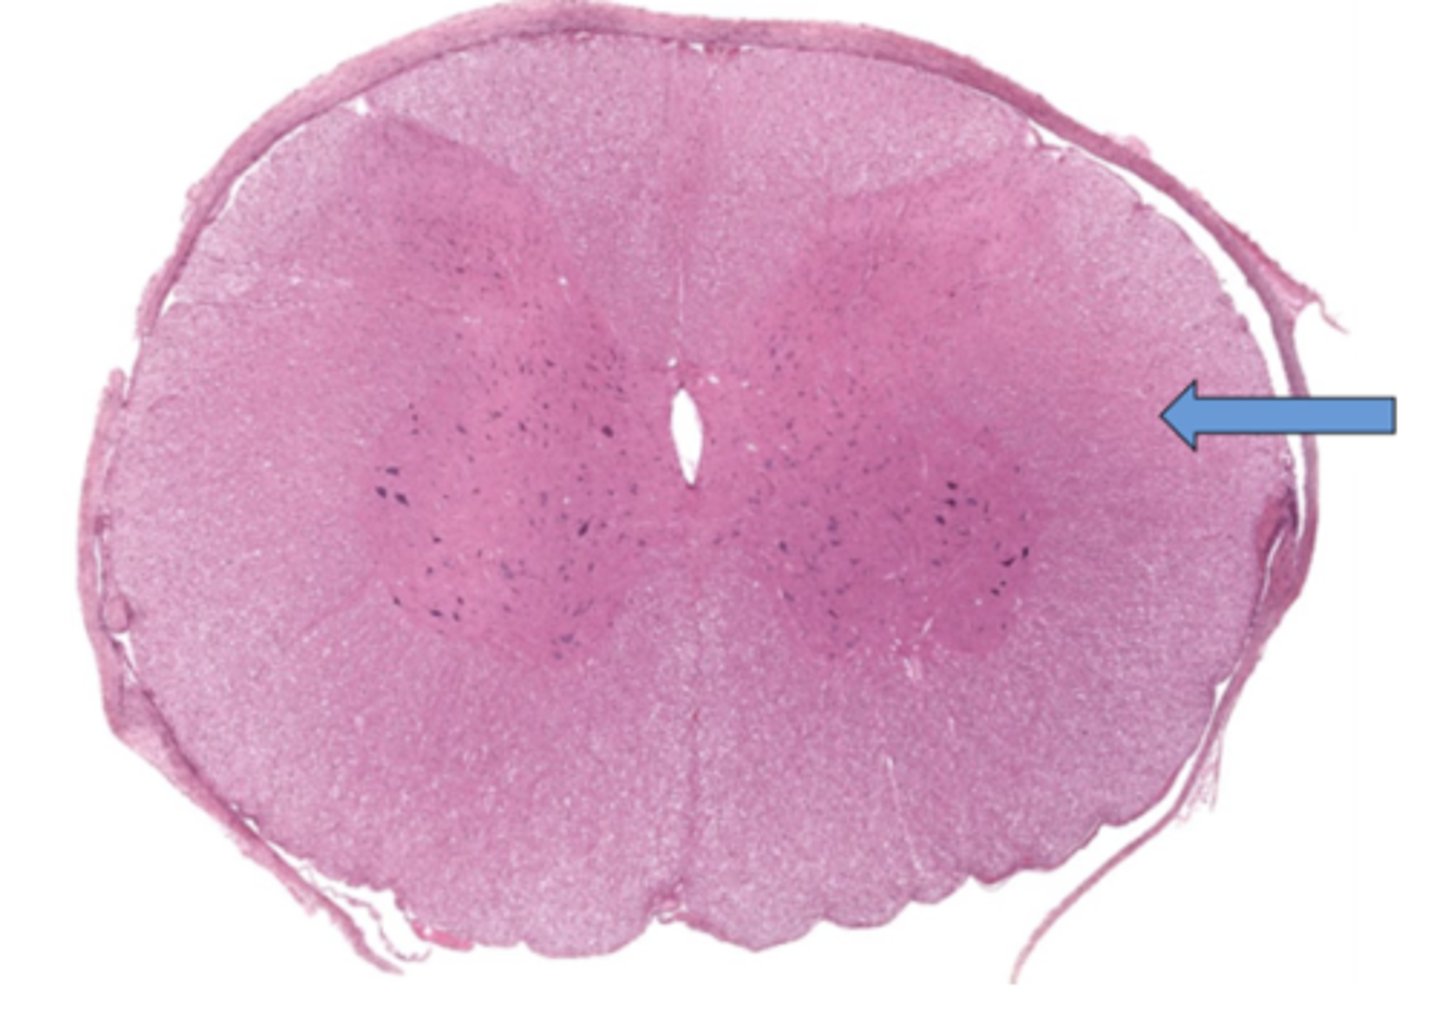

Identify the part of the spinal cord

dorsal funiculi

lateral funiculi

ventral funiculi

dorsal horn

ventral horn

dorsal root of spinal nerve

ventral root of spinal nerve

What is the midline structure that separates the dorsal left and right halves of the white matter

dorsal median septum

What is the midline structure that separates the ventral left and right halves of the white matter

ventral median sulcus

Identify the section of the spinal cord that contains nuclei

gray matter

Identify the section of the spinal cord that contains nerve tracts

white matter

central canal